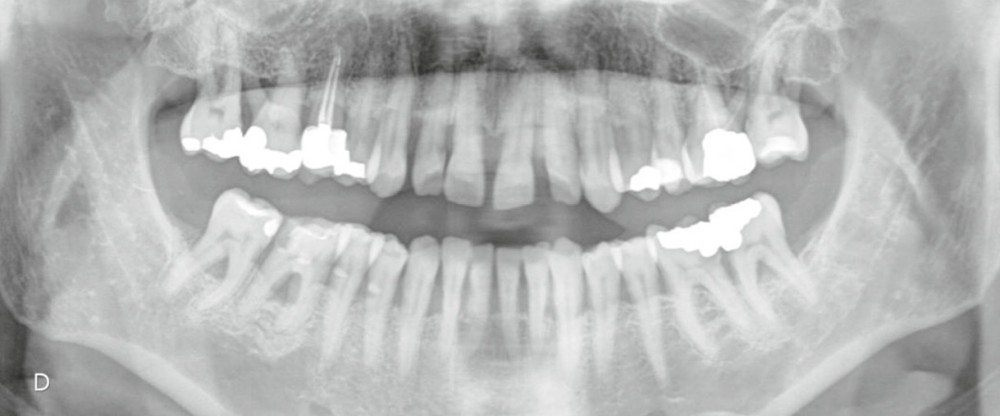

L’examen radiographique (fig. 3-5) nous indique une Classe I squelettique de Ballard (ANB 0°) sur un schéma facial à tendance hyperdivergent (FMA 28°). L’analyse céphalométrique confirme la vestibulo-version incisive (I/SN 111° ; IMPA 94°). La lyse osseuse est généralisée.